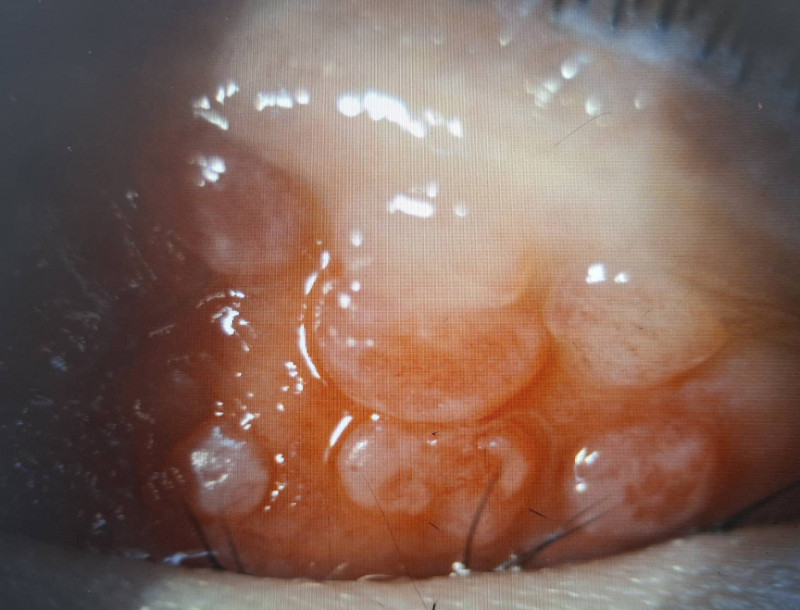

小二男童因長期眼睛癢揉眼,結膜炎導致左上眼瞼出現多顆巨大乳突。(洪啟庭提供)

男童因結膜慢性發炎,使結膜上皮細胞的過度增生,長成大於0.1公分的乳突。(洪啟庭提供)

巨大乳突壓迫不僅造成角膜潰瘍,還出現高度散光而視力模。(洪啟庭提供)